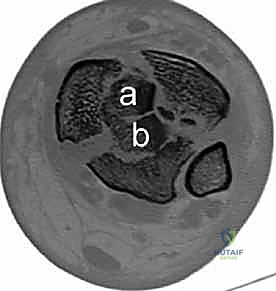

2. التصوير المقطعي المحوسب (CT Scan) - المعيار الذهبي

لا يمكن إجراء جراحة حديثة لكسر البيلون دون إجراء أشعة مقطعية. لماذا؟

كشفت الأبحاث المتقدمة (مثل أبحاث كول Cole وزملائه) والتي يعتمد عليها الدكتور هطيف، أن الأشعة المقطعية، وخاصة مع إعادة البناء ثلاثي الأبعاد (3D Reconstruction)، تسمح برسم خريطة دقيقة لكل قطعة عظمية مفتتة في السطح المفصلي (AO/OTA 43-C3).

تظهر الأشعة المقطعية النمط الثابت لتفتت البيلون والذي يتكون عادة من ثلاث قطع رئيسية:

* القطعة الأمامية الجانبية (Chaput fragment): متصلة بالرباط الظنبوبي الشظوي الأمامي.

* القطعة الخلفية (Volkmann fragment): متصلة بالرباط الظنبوبي الشظوي الخلفي.

* القطعة الأنسية (Medial Malleolus): متصلة بالرباط الدالي.

وفي الوسط، توجد منطقة "الانهيار المفصلي" (Die-punch fragment) التي تُدفع داخل العظم.

يستخدم الأستاذ الدكتور محمد هطيف هذه الخريطة المقطعية لتحديد مسار الشقوق الجراحية، واختيار أحجام وأنواع الشرائح المعدنية المطلوبة، وتحديد تسلسل إرجاع القطع العظمية قبل دخول غرفة العمليات.